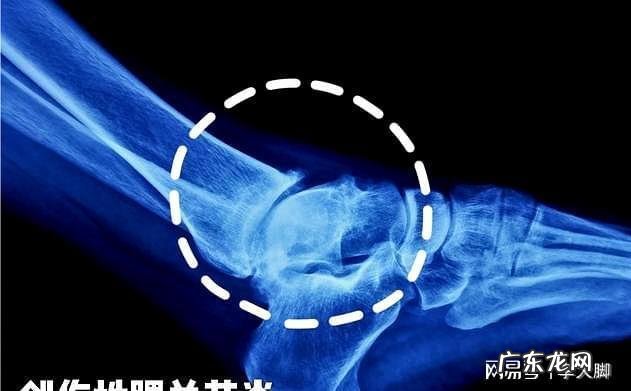

压腿时韧带拉伤怎么办压腿开叉之前都 要先热身 , 因为天气冷韧带收缩的紧 , 有时候它一下子就下去了,有时候下不去,主要还是韧带没有完全拉开,还是要多练 , 过几天就好了,没关系的不用烦恼 。